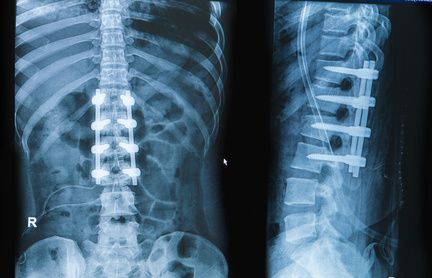

Auch eine Spondylodese (Versteifungsoperation oder Fusion) kann bei einer Spinalkanalstenose sinnvoll sein. Ist eine Überbeweglichkeit der Wirbelsäule durch Gleitwirbel (Spondylolisthesis) die Ursache der spinalen Stenose, reicht eine reine Dekompression häufig nicht aus. Nur eine Spondylodese, eine Fusion der Wirbelkörper, die das betreffende Bandscheibensegment bilden, eignet sich in diesem Fall für eine Therapie. Die Spondylodese stabilisiert die Position der Wirbelkörper zueinander dauerhaft und stoppt das einengende Wirbelgleiten. Wenn Bedarf besteht, lässt sich die Spondylodese mit einer Dekompression (operativen Weitung des Wirbelkanals) kombinieren.

In manchen Fällen reicht das Abtragen von störenden Strukturen oder eine Versteifung nicht aus, um Druck vom Nervengewebe zu nehmen. Dann sind sog. Cages eine Option. Sie werden z. B. im Rahmen einer Fusionsoperation (Spondylodese) als Platzhalter in das Bandscheibenfach zwischen zwei Wirbelkörpern eingesetzt. Dort kann der Cage aufgespreizt werden und sich einklemmen. Auf diese Weise hilft er, zwischen den Wirbelkörpern einen ausreichenden Abstand und den Druck vom Nervengewebe zu halten.

Eine weitere Möglichkeit ist das Implantieren von interspinösen Spreizern, auch Wirbelsäulenspreizer genannt. Dabei handelt es sich um kleine, z. B. X-förmige Metallimplantate. Sie setzt man im Bereich der Spinalkanalstenose zwischen den Dornfortsätzen der Wirbelkörper ein. Dort sollen sie der starken Beugung der Lendenwirbelsäule entgegenwirken und dadurch den Wirbelkanal offen halten und die Nerven entlasten. Weil im Gegensatz zur Versteifung im betroffenen Segment weiter eine gewisse Beweglichkeit möglich ist, spricht man auch von einer dynamischen Stabilisierung. In ihrer Wirkung sind Wirbelsäulenspreizer allerdings relativ unsicher. Vor allem die langfristigen Ergebnisse fallen recht unterschiedlich aus. Mittelfristig führt die Implantation zur verstärkten Abnutzung der Nachbarsegmente. Zudem ist das Verfahren für viele Patienten nicht geeignet, z. B. wenn sie unter Osteoporose leiden oder Gleitwirbel haben.

Die Operation der Lendenwirbelsäule erfolgt in Bauchlage oder seitlicher Lagerung. Zur Öffnung des Operationsgebietes führt der Arzt einen etwa 6 cm langen Hautschnitt entlang der Wirbelsäule durch. Nach der Freilegung der Wirbelsäule werden zunächst eventuelle Knochenanbauten (Spondylophyten) an den Wirbelgelenken entfernt.

Dann erweitert der Rückenspezialist den Raum zwischen den betroffenen Dornfortsätzen der Wirbelsäule mit einem Dilatator und positioniert das Implantat. Je nach Ausmaß der Spinalkanalstenose stehen verschiedene Größen des Abstandhalters zur Verfügung. Die korrekte Position überprüft der Arzt mittels Röntgenbild. Ziel des Eingriffs ist die Dekompression (Entlastung) der Nerven und damit die Aufhebung von Lähmungen, Gefühls- und Bewegungsstörungen und Schmerzen.